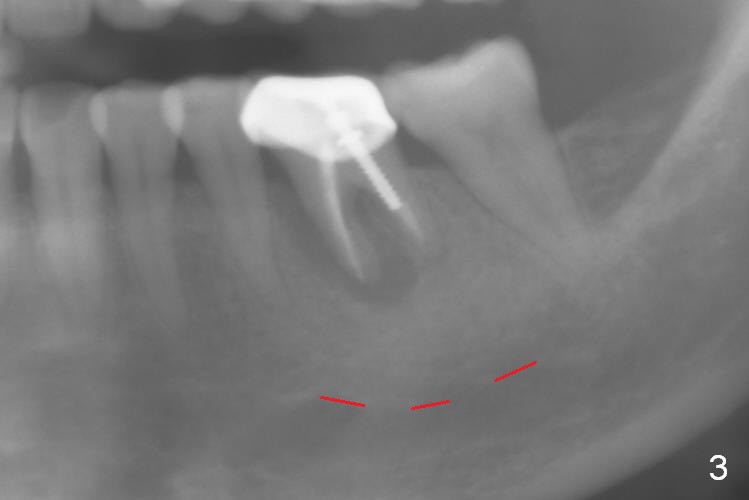

A 58-year-old lady has a long-standing periapical lesion with several episodes of acute infection (Fig.1-3, taken 10, 9 and 2 years ago, respectively). Explore the socket for size and wall integrity (Clindamycin). If the bony defect is not extensive, place a longest implant (18 mm bone-level, 20 mm tissue-level) with moderate diameter (5.5, 6 mm). Otherwise use a shorter, but wider tapered implant (7x12 mm (bone-level), 7 or 8x17 mm (tissue-level)). If the socket is extremely large, consider using 7 or 8 x20 mm cylindrical tissue-level implant. Use Bicon 2 mm pilot drill with extension to measure the socket depth and obtain 3-6 mm new bone or until 20 mm (gingival margin). Take PA. The 1st option is to use UF 3-4.7x18 mm drills at 50 RPM. Make sure that the depth is reached (septum crestal level) and check osteotomy wall integrity after each drill. Then place a 5 or 5.5x16 or 18 mm implant (Fig.6). The 2nd and 3rd options are shown in Fig.4 and 5. Due to severe infection and pain, a shorter implant is placed.